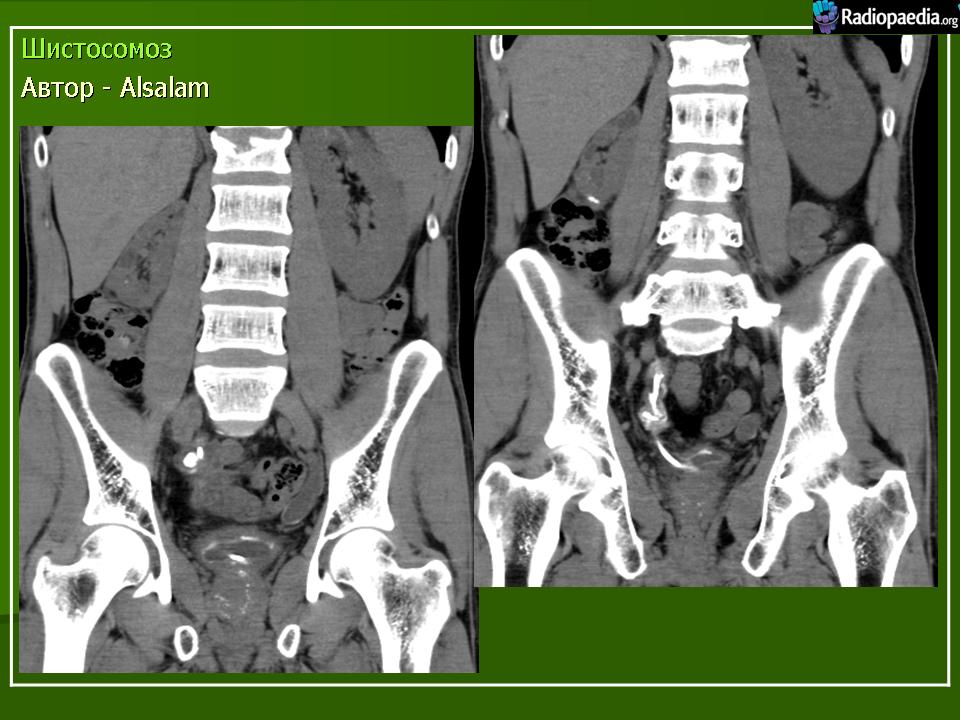

Бильгарциоз (Schistosomiasis) мочевого пузыря